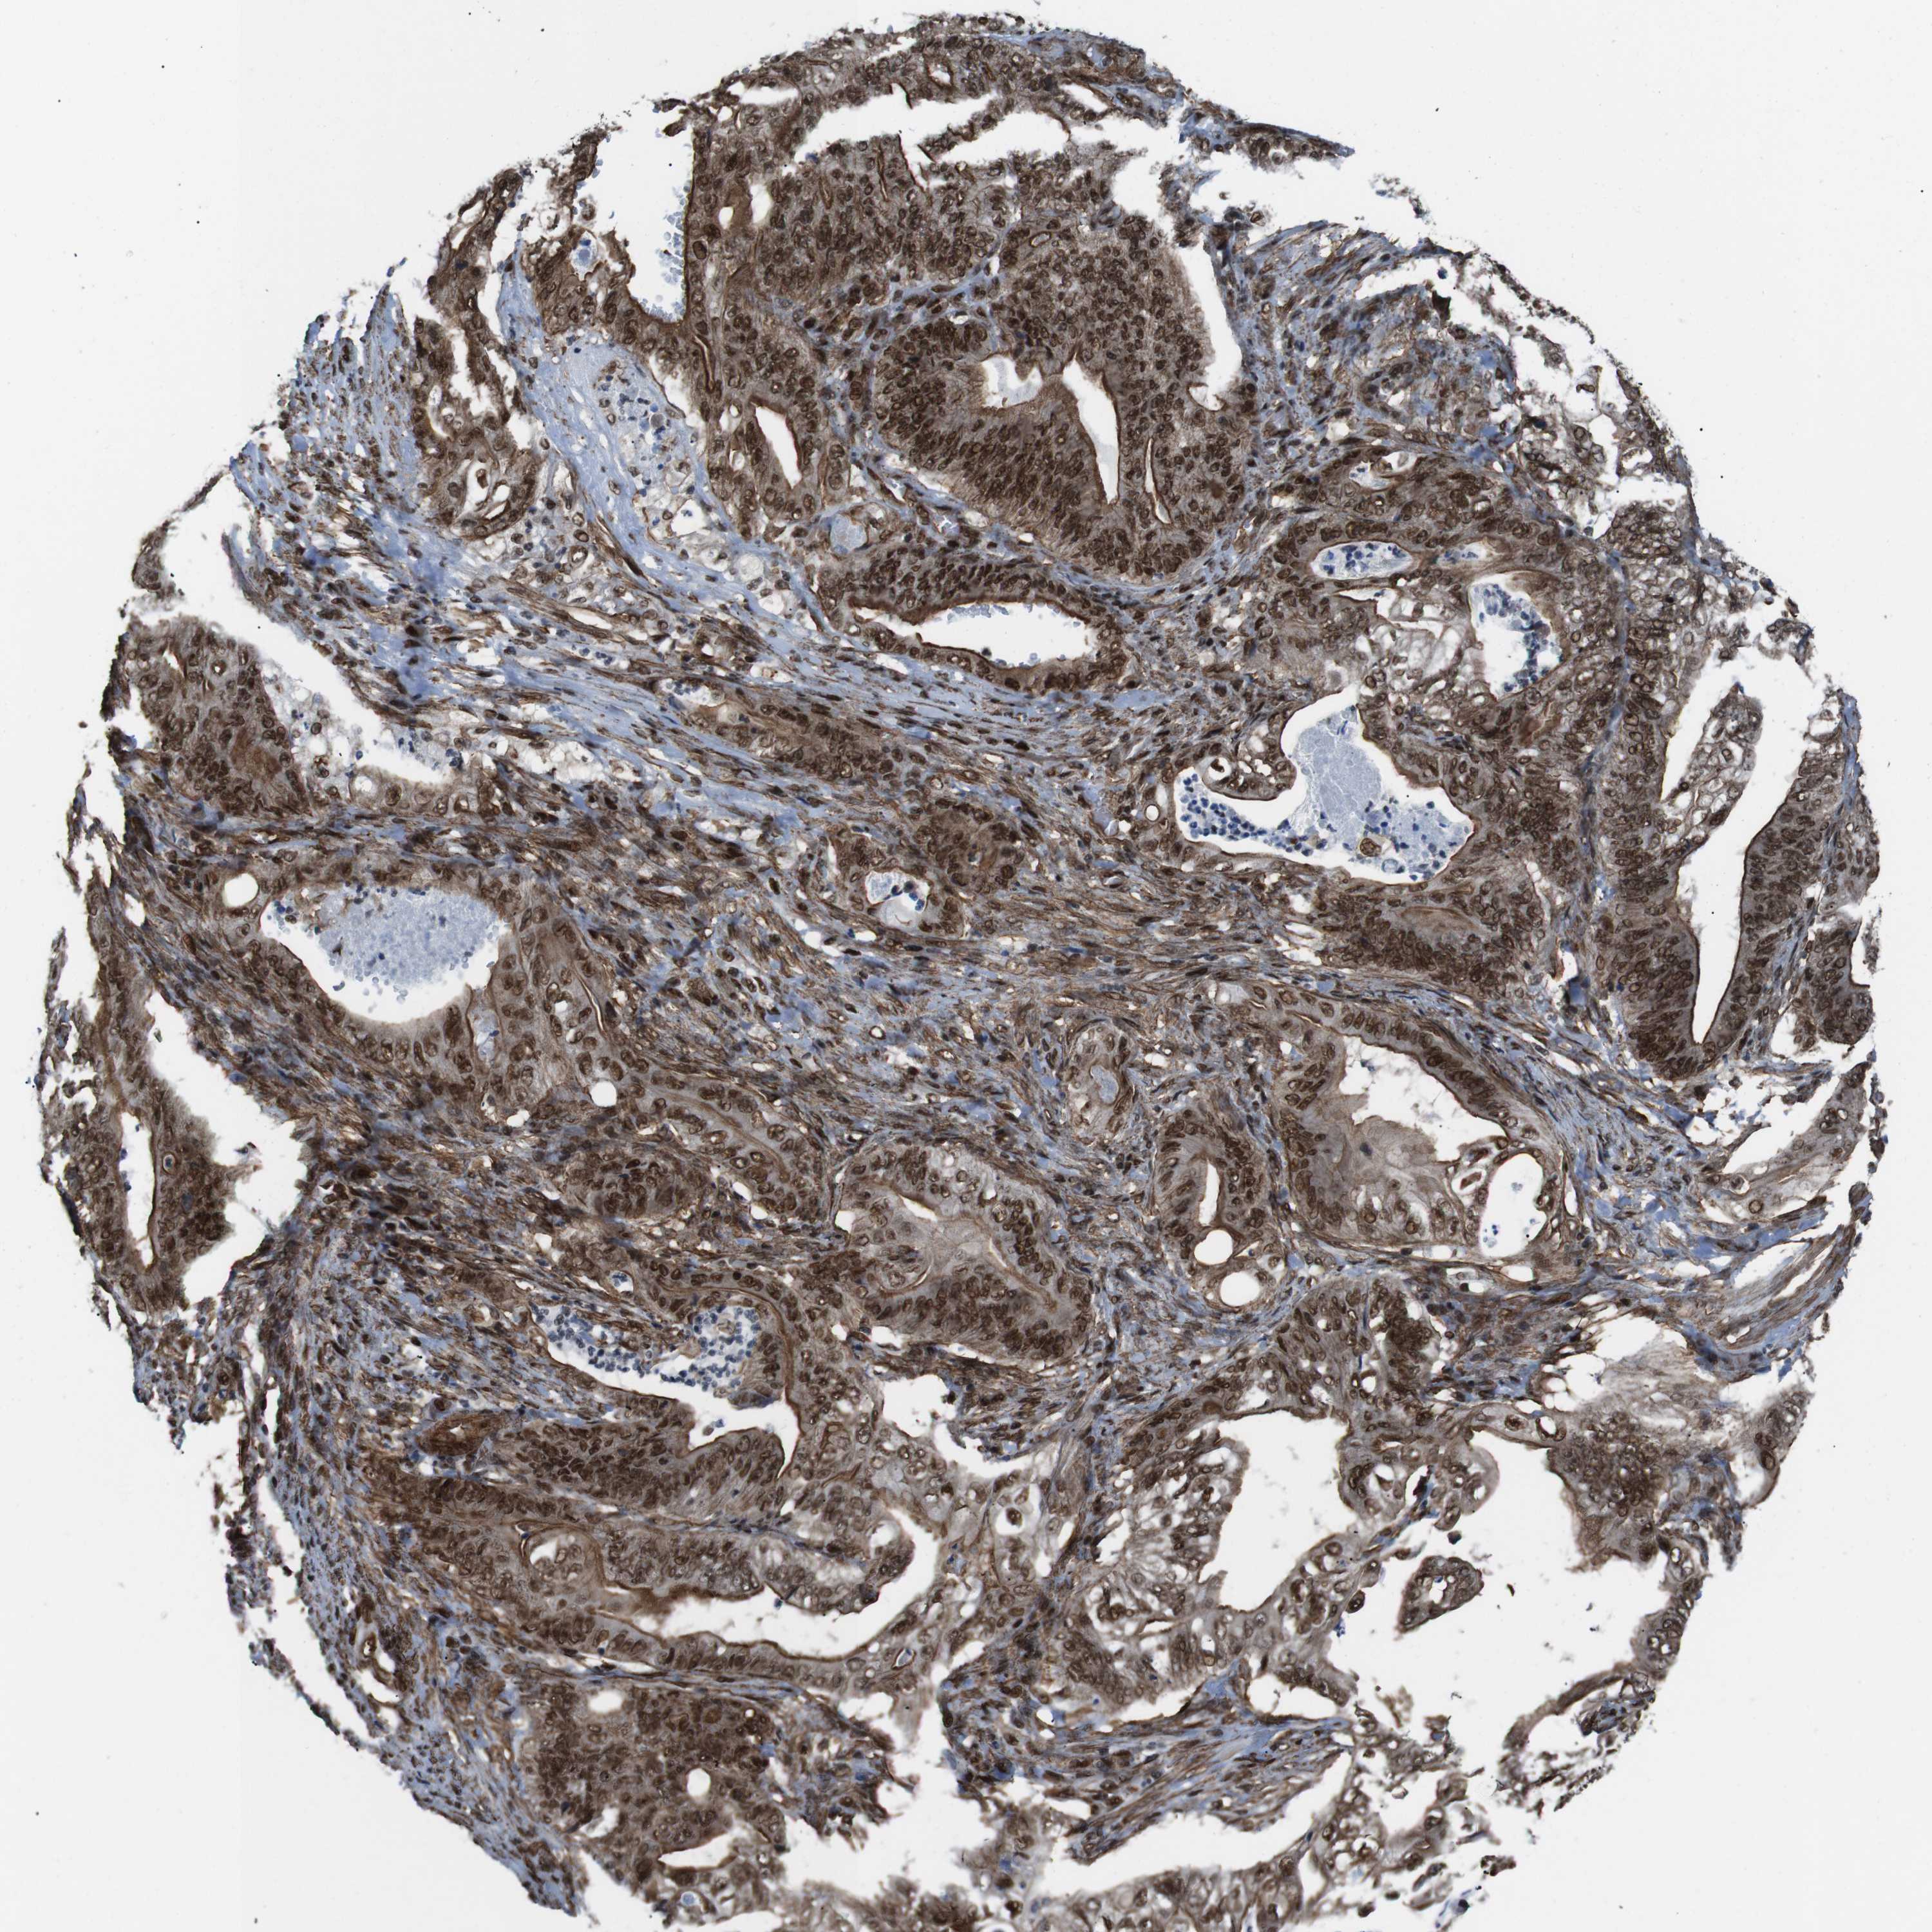

STOMACH CANCER - Protein expressioni

A mouse-over function shows sample information and annotation data. Click on an image to view it in a full screen mode. Samples can be filtered based on level of antibody staining by selecting one or several of the following categories: high, medium, low and not detected. The assay and annotation is described here.

Note that samples used for immunohistochemistry by the Human Protein Atlas do not correspond to samples in the TCGA dataset.

Antibody stainingi

Antibody staining in the annotated cell types in the current human tissue is reported as not detected, low, medium, or high, based on conventional immunohistochemistry profiling in selected tissues. This score is based on the combination of the staining intensity and fraction of stained cells.

Each image is clickable and will lead to virtual microscopy that enables deeper exploration of all samples and also displays staining intensity scores, fraction scores and subcellular localization as well as patient and tissue information for each sample.

Antibody HPA041057

Antibody HPA058707

Antibody CAB011532

Staining

High

Medium

Low

Not detected

Intensity

Strong

Moderate

Weak

Negative

Quantity

>75%

75%-25%

<25%

None

Location

Nuclear

Cytoplasmic/membranous

Cytoplasmic/membranous,nuclear

Adenocarcinoma, NOS

Adenocarcinoma, High grade